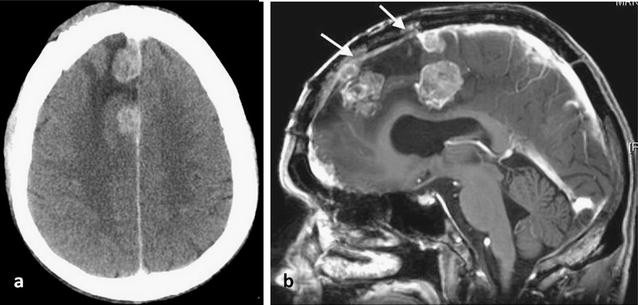

A 55 year old man was admitted to hospital with a head injury that resulted in hearing loss on the left side with pulsatile tinnitus and a vague feeling of disorientation. A CT scan showed an irregular extra-axial solitary lesion lying adjacent to the falx on the right of the midline measuring 3 × 4 × 6 cm with significant mass-effect and peritumoral oedema involving most of the right frontal lobe. There was evidence of underlying bone remodelling with vascular dural supply and heterogeneous enhancement after contrast administration with a deep cystic component. There were fringes of tumour interdigitating with the brain substance indicating probable brain invasion (Fig. 1). The findings were consistent with an aggressive frontal meningioma. Partial surgical removal of the lesion in the right frontal lobe was undertaken. On histological examination, the lesion was classified as an atypical (WHO Grade II) meningotheliomatous meningioma.

Axial CT post contrast image (a) and sagittal reconstruction (b) shows an irregular extra-axial solid mass with heterogeneous enhancement and deep cystic change (arrow) adjacent to the falx extending into the right frontal lobe. There is significant peritumoral oedema and mass effect involving the right frontal lobe with displacement of the midline. These findings, together with tumour interdigitating with the brain substance, are consistent with an aggressive frontal meningioma

A year later, the patient experienced an episode of seizures and a CT scan revealed three new lesions at the site of the previously excised meningioma with extensive perilesional oedema. An MRI confirmed the CT findings indicative of tumour and also detected invasion and occlusion of the anterior part of the superior sagittal sinus (Fig. 2). Partial resection of the recurrent mass was again undertaken. Histology of the tumour specimen showed features of an anaplastic (WHO Grade III) meningotheliomatous meningioma with lobules of tumour containing cells with round or oval vesicular nuclei. Focally, there were cells which showed more prominent nuclear pleomorphism. There was increased mitotic activity and extensive tumour necrosis was noted (Fig. 3). Post-operative follow-up revealed residual tumour in the anterior part of the superior sagittal sinus, along the falx and the right frontal convexity. Follow-up imaging also confirmed interval progression of the residual meningioma.

Axial CT post contrast image showing: a nodular enhancing masses and perilesional oedema in the right frontal lobe, indicative of local recurrence of the meningioma. b A sagittal T1-weighted MR image post contrast confirming the presence of three lesions and invasion of the superior sagittal sinus (arrows)